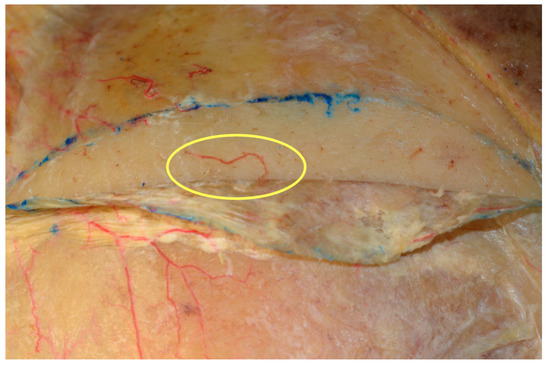

During the cadaveric study, it was possible to isolate and follow the entire paths of the bilateral STA and STV. Sixteen flaps were prepared. The anatomical blood supply to the pericranial parieto-temporal region appeared to arise from the superficial temporal vessels and reached the cranial bone via perforator vessels, as shown in Figure 8.

Figure 8.

The anatomical blood supply to the parieto-temporal pericranial region. Perforators arising from superficial temporal vessels are visible in both embalmed and fresh cadavers.

The maximum width of the temporoparietal flap was 15 cm; the appropriate width for each patient depended on the vascular pattern of the STA. The average vessel diameter was 4 mm and the average pericranial flap was 7 cm × 12 cm (range: 6–8 cm × 10–13 cm). When required, the lateral extension provides adequate soft tissue bulk for oral reconstruction. The range of flap rotation was also tested; the flap easily reached the maxillary, cheek, and ipsilateral mandibular regions.